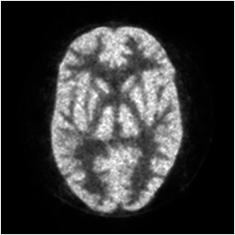

2.2.6. Clinical and pre-clinical studies.

Clinical and pre-clinical studies were performed at Hamamatsu University School of Medicine. All animal and human experiments were approved by the Ethics Committees of Hamamatsu University School of Medicine. In the clinical study, a healthy volunteer was scanned for 62 min after the injection of 246.4 MBq of 11C-MeQAA, a tracer for α7 nicotinic acetylcholine receptors. The images were reconstructed using the LM-DRAMA in both HR and HS-modes with four iterations. Attenuation with E-SAC and scatter corrections were employed, and images were processed with and without application of post-smoothing. As pre-clinical studies, 18F-FDG rat and mouse imaging studies were performed. A SD rat (8 weeks, 270.7 g) was scanned for 15 min after 45 min post-injection of 34.7 MBq of 18F-FDG, and a ddY mouse (7 weeks, 27.6 g) was also scanned for 60 min after the injection of 44.0 MBq of 18F-FDG. These animals were anesthetized by intravenous injection of chloral hydrate, and were then placed at the center of the FOV. The images were reconstructed using the LM-DRAMA in the HR-mode with four iterations, and the voxel size in the image matrix was 0.2 × 0.2 × 0.6 mm3. Attenuation with E-SAC and scatter corrections were employed, but no post-smoothing was applied to the images.

Figures 13(a)–(c) show human brain images of a slice from a healthy volunteer given 11C-MeQAA, with reconstruction (a) in the HR-mode without post-smoothing, (b) in the HR-mode with post-smoothing, and (c) in the HS-mode without post-smoothing, respectively. All 62 min acquisition data were used for the reconstruction. The total true coincidence counts, including scatter events, for image reconstruction were 534 M counts. The HR-mode image (a) appears to be of high resolution, if slightly noisier than the HS-image (c), given the small voxel size of the image matrix and lack of post-smoothing. Therefore, block-matching and 4D filter (BM4D) (Maggioni et al 2013) was applied to the image in (a) for post-smoothing, to derive a denoising image (b). Figure 14 shows 18F-FDG (a) rat and (b) mouse images in the transverse, coronal, and sagittal directions. For image reconstruction, all 15 min acquisition data for the rat and the last 15 min of data from among the 60 min acquisition data for the mouse were used. The cerebral cortex in the rat brain was clearly observed, and that in the mouse brain was visible.

Figure 13. The same brain slices of 11C-MeQAA PET images of a healthy volunteer using different reconstruction modes: (a) high-resolution (HR)-mode, (b) HR-mode plus post-smoothing with a block-matching and 4D filter, (c) high-speed (HS)-mode.

The detector resolution was evaluated by measuring the CRFs and the average FWHM value of 1.08 mm and 1.25 mm for 0° and 22.5° in the first layer pair, respectively, were obtained. The system spatial resolution was less than 2.1 mm FWHM across the whole FOV, measured according to NEMA NU 2-2012. In the HR-mode when using LM-DRAMA, 1.35 mm hot-spots in an ultra-micro hot-spot phantom were clearly separated. To evaluate the imaging capabilities, we performed measurements on a 3D Hoffman phantom, a human brain, and small animals. We obtained clear images, as shown in figures 12–14.